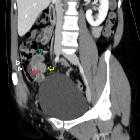

Endometriosis

of the Appendix. Coronal modified view better depits the relation of the appendiceal mass (yellow arrow) with the ileum (green arrowhead), appendix (red arrow pinpointing the air bubble in its lumen) and the cecum (white arrowheads)